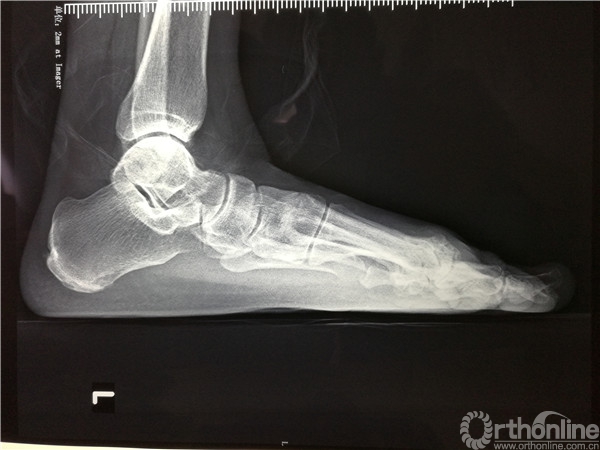

2016年4月7日,烟台市烟台山医院南院骨科收治一例左足跖趾关节骨性关节炎的病人,患者左足严重疼痛10余年,要求治疗的心情迫切。

在张树栋院长及刘克贵主任的支持下,南院骨科组织多次病例讨论,制定了一套对病人有效的治疗方案。以刘克贵主任,孙冰,李宏彦组成的医疗小组。于2016年4月9日上午九时,在腰麻下行左足第1、2 跖趾关节人工关节置换术,患者术后左足的疼痛明显减轻,功能良好,外形美观。